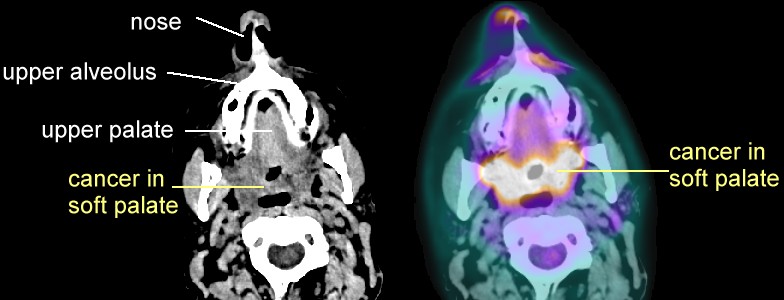

- Soft palate:

PET/CT

here and

here